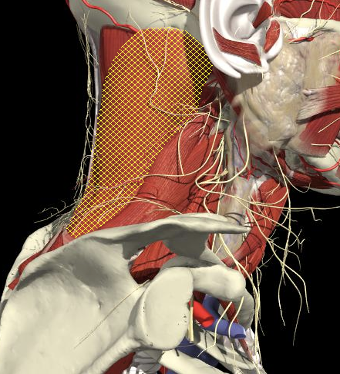

Structures to Avoid

Nerves in Posterior Triangle

Accessory nerve

Inject levator above this point

Landmarks

Cervical plexus

Midpoint of SCM (EP)

Middle and lower third of Trapezius

Arteries

- Carotid artery

Midpoint anterior border of SCM

Vertebral artery

- Occipital bone or C2 towards midline is safe

Occipital artery

Avoid apex of posterior triangle